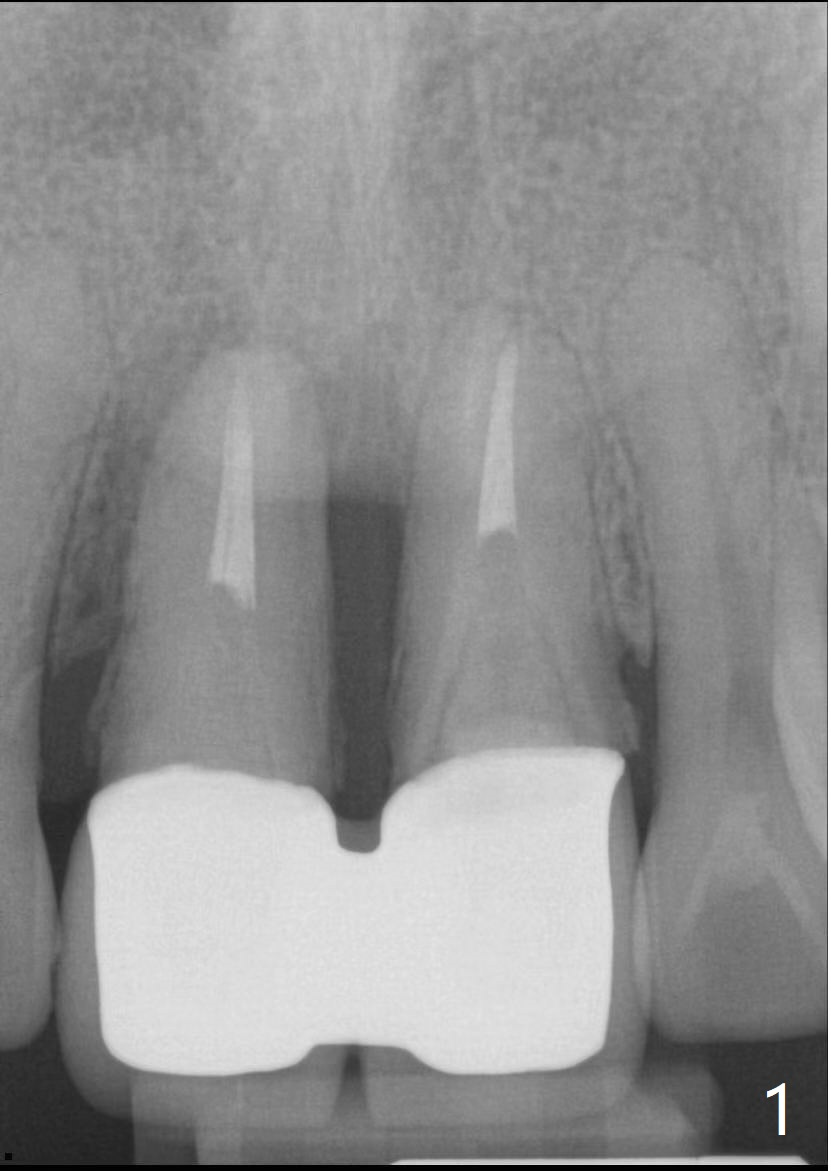

40几岁,身体无其它疾病(图一),全面检查,包括CT,取模做suck down stent/临时牙冠。